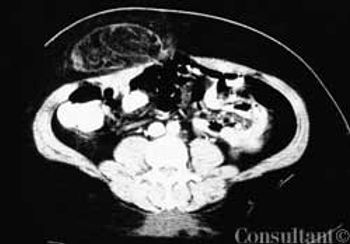

For 2 months, a 73-year-old man had experienced dysuria, pneumaturia, and foul-smelling urine. He had an attack of diverticulitis a year earlier. At that time, he underwent a barium enema study, which showed multiple sigmoid colonic diverticula with spasm.